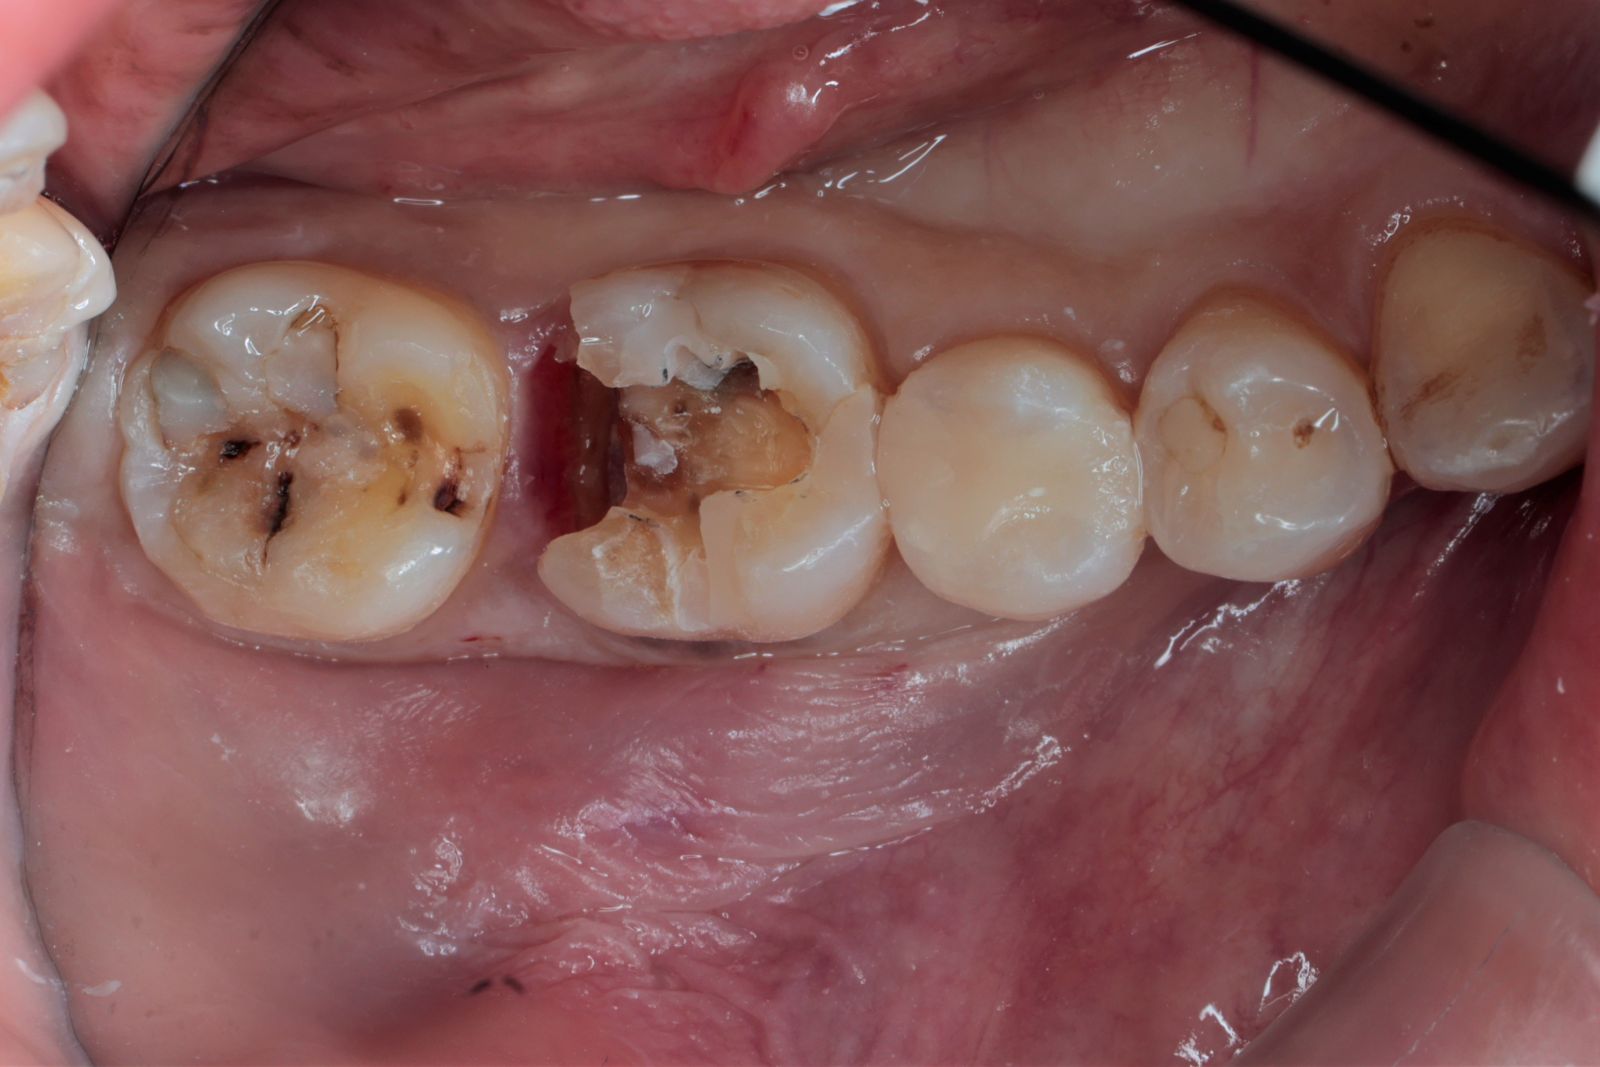

【 案 例 一 】

- 以前大範圍的樹脂補牙,久了造成二次蛀牙,不只是材料不密合,原本的牙齒還可能斷裂。把蛀牙挖乾淨後,隔絕感染源再印模,待陶瓷齒雕送回後再以特殊黏膠黏著完成!經過全陶瓷齒雕修復後,跟原先相比之下,牙齒恢復外型以外還能增強牙齒強度。